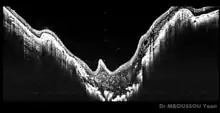

Dans le syndrome du liseron, la papille forme une sorte d'excavation en entonnoir. Celle-ci est occupée par une masse de tissu glial plus ou moins importante, d'un anneau pigmenté péripapillaire, et les vaisseaux sont organisés selon une disposition radiaire[2]. Plusieurs formes cliniques existent[2].